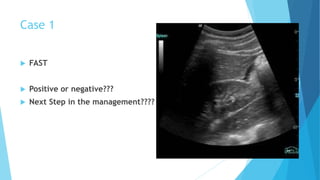

Ultrasonography

 The focused abdominal sonography for trauma (FAST) emerged

recently as an important tool in the initial diagnosis of intra-

abdominal injuries.

 Performed by surgeons or emergency room physicians, FAST has

shown an excellent sensitivity in identifying intra-abdominal fluid.

 Because of its ease of use, repeatability, and avoidance of radiation

exposure it has rapidly become an essential part of the initial

evaluation.

 In the presence of multiple Intraperitoneal injuries, blood is most

often found by FAST in the right upper quadrant.

 At this point, it seems that the most significant contribution of the

FAST examination is in the detection of intra-abdominal fluid in the

hemodynamically unstable and clinically unevaluable blunt trauma

victim.

 These patients should be immediately taken to the operating room for

abdominal exploration.

 Negative FAST exams do not preclude the need for further evaluation of

the abdomen by other imaging modalities, most commonly computed

tomography (CT).

Case 1

 FAST

 Positive or negative???

 Next Step in the management????